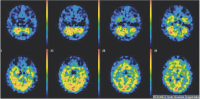

Abbildung 5: Single Photon Emission Computed Tomography- (SPECT-) Szintigraphie des Gehirns 10 min. nach i.v.-Applikation von 555 MBq 99m-Tc- NEUROLITE): Inhomogen abgeschwächte Anreicherung am Großhirnkortex beidseits.

SPECT-Szintigraphie